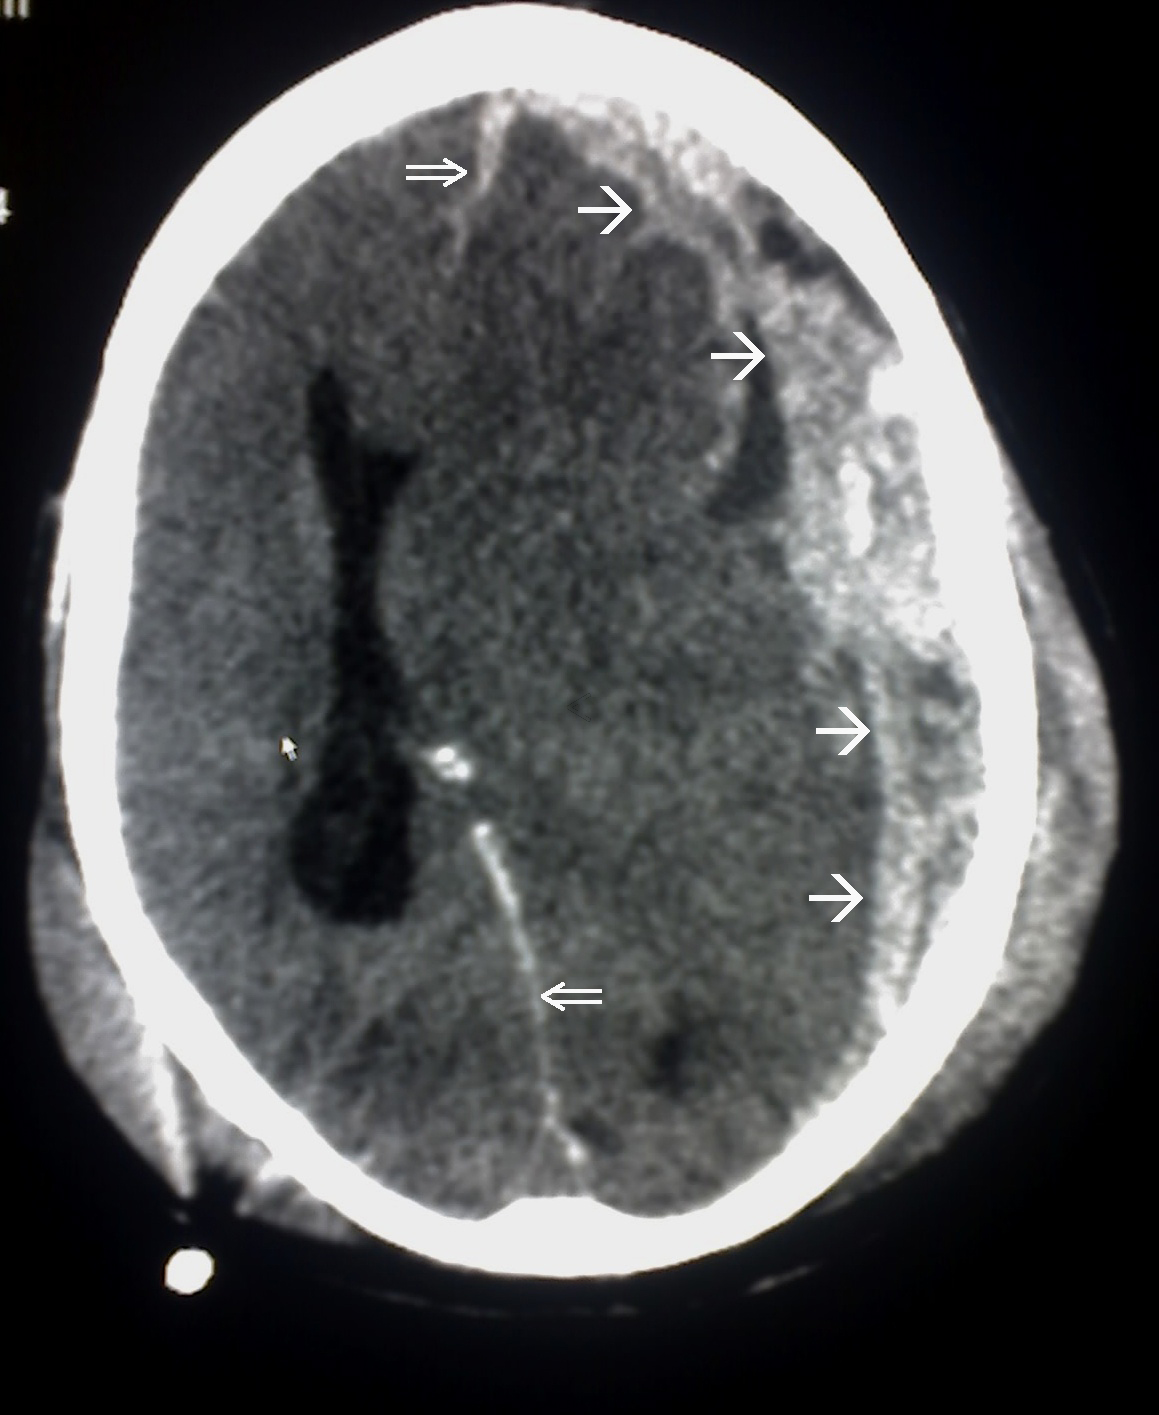

외상성 뇌손상(TBI)의 진단은 병변의 상황과 임상 증거, 특히 신경학적 검사 결과를 바탕으로 의심된다.[162] 신경 영상 검사는 진단 및 예후를 결정하고 적절한 치료법을 결정하는 데 중요한 보조 수단으로 활용된다.[165] 또한, DSM-5는 외상성 뇌손상과 관련된 정신과적 후유증을 진단하는 데 사용될 수 있다.[69][70][71]

신경 영상 검사는 외상성 뇌손상의 진단 및 예후를 결정하고 적절한 치료법을 결정하는 데 도움이 된다.[165]

응급 상황에서는 컴퓨터 단층촬영(CT)이 가장 선호되는 방사선 검사다. 신속하고 정확하며 널리 사용 가능하기 때문이다.[73] 손상이 진행되었는지 확인하기 위해 추후 CT 촬영을 실시할 수도 있다.[193]

자기공명영상(MRI)은 CT보다 더 자세한 정보를 보여주며 장기적인 예후에 대한 정보를 추가할 수 있다.[162] 특히 확산성 축삭 손상과 같은 손상 특징을 감지하는 데 CT보다 유용하다.[193] 하지만 MRI는 응급 상황에서는 출혈 및 골절 감지의 상대적 비효율성, 영상 획득 시간이 길다는 점, 기계 내 환자의 접근성 문제, 응급 치료에 사용되는 금속 물체와의 비호환성 등의 이유로 잘 사용되지 않는다.[162] 2012년 이후 MRI의 변형 기술로 고해상도 섬유 추적(HDFT)이 있다.[72]